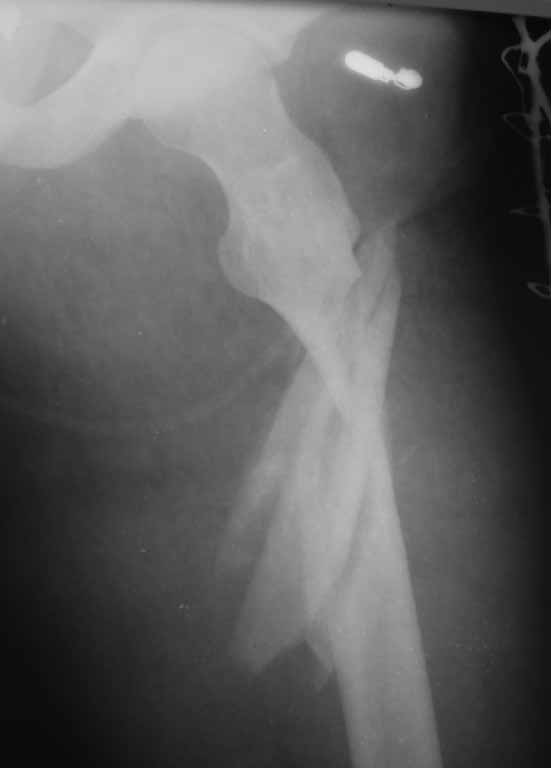

подвертельный перелом - тактика лечения? |

Уважаемые коллеги!!! Ваши предложения по тактике лечения, планируется закрытая репозиция, ИМОС AFN, кто встречался с подобным, какие могут быть сложности интраоперационно

Подвертельный оскольчатый перелом. Если пострадавший относительно молод, нет остеопороза, лучше реконструкционный гвоздь. Успешная репозиция очень важна. С помощь тракционного стола или дистрактора таз-бедро она легко достигается. Остаточный варус - самая распространенная ошибка. Точка входа не должна быть слишком латеральной, даже если гвоздь с проксимальным изгибом. Гвоздь должен идти близко к латеральной стенке центрального отломка.

Аналогичный перелом, синтезировали длинной Гаммой stryker, точка введения через верхушку вертела удобней и безопасней, чем у AFN.